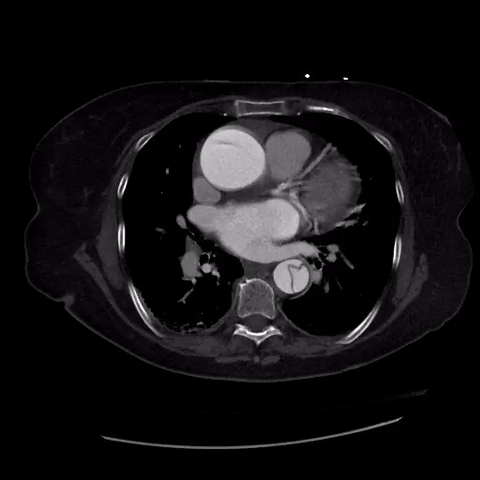

CT Thorax with angiogram

In this case, POCUS resulted in the early diagnosis and prompt treatment of

TA-AAD. Cardiothoracic surgery was immediately consulted, and after correcting

her supratherapeutic INR, she was taken to the OR for emergent surgery. She

received a bioprosthetic aortic valve and her aortic root was replaced with a

synthetic graft. Her left atrial appendage was excluded with a clip to lower

her long-term risk of stroke in the setting of atrial fibrillation. She had an

uneventful recovery and was discharged home in stable condition.